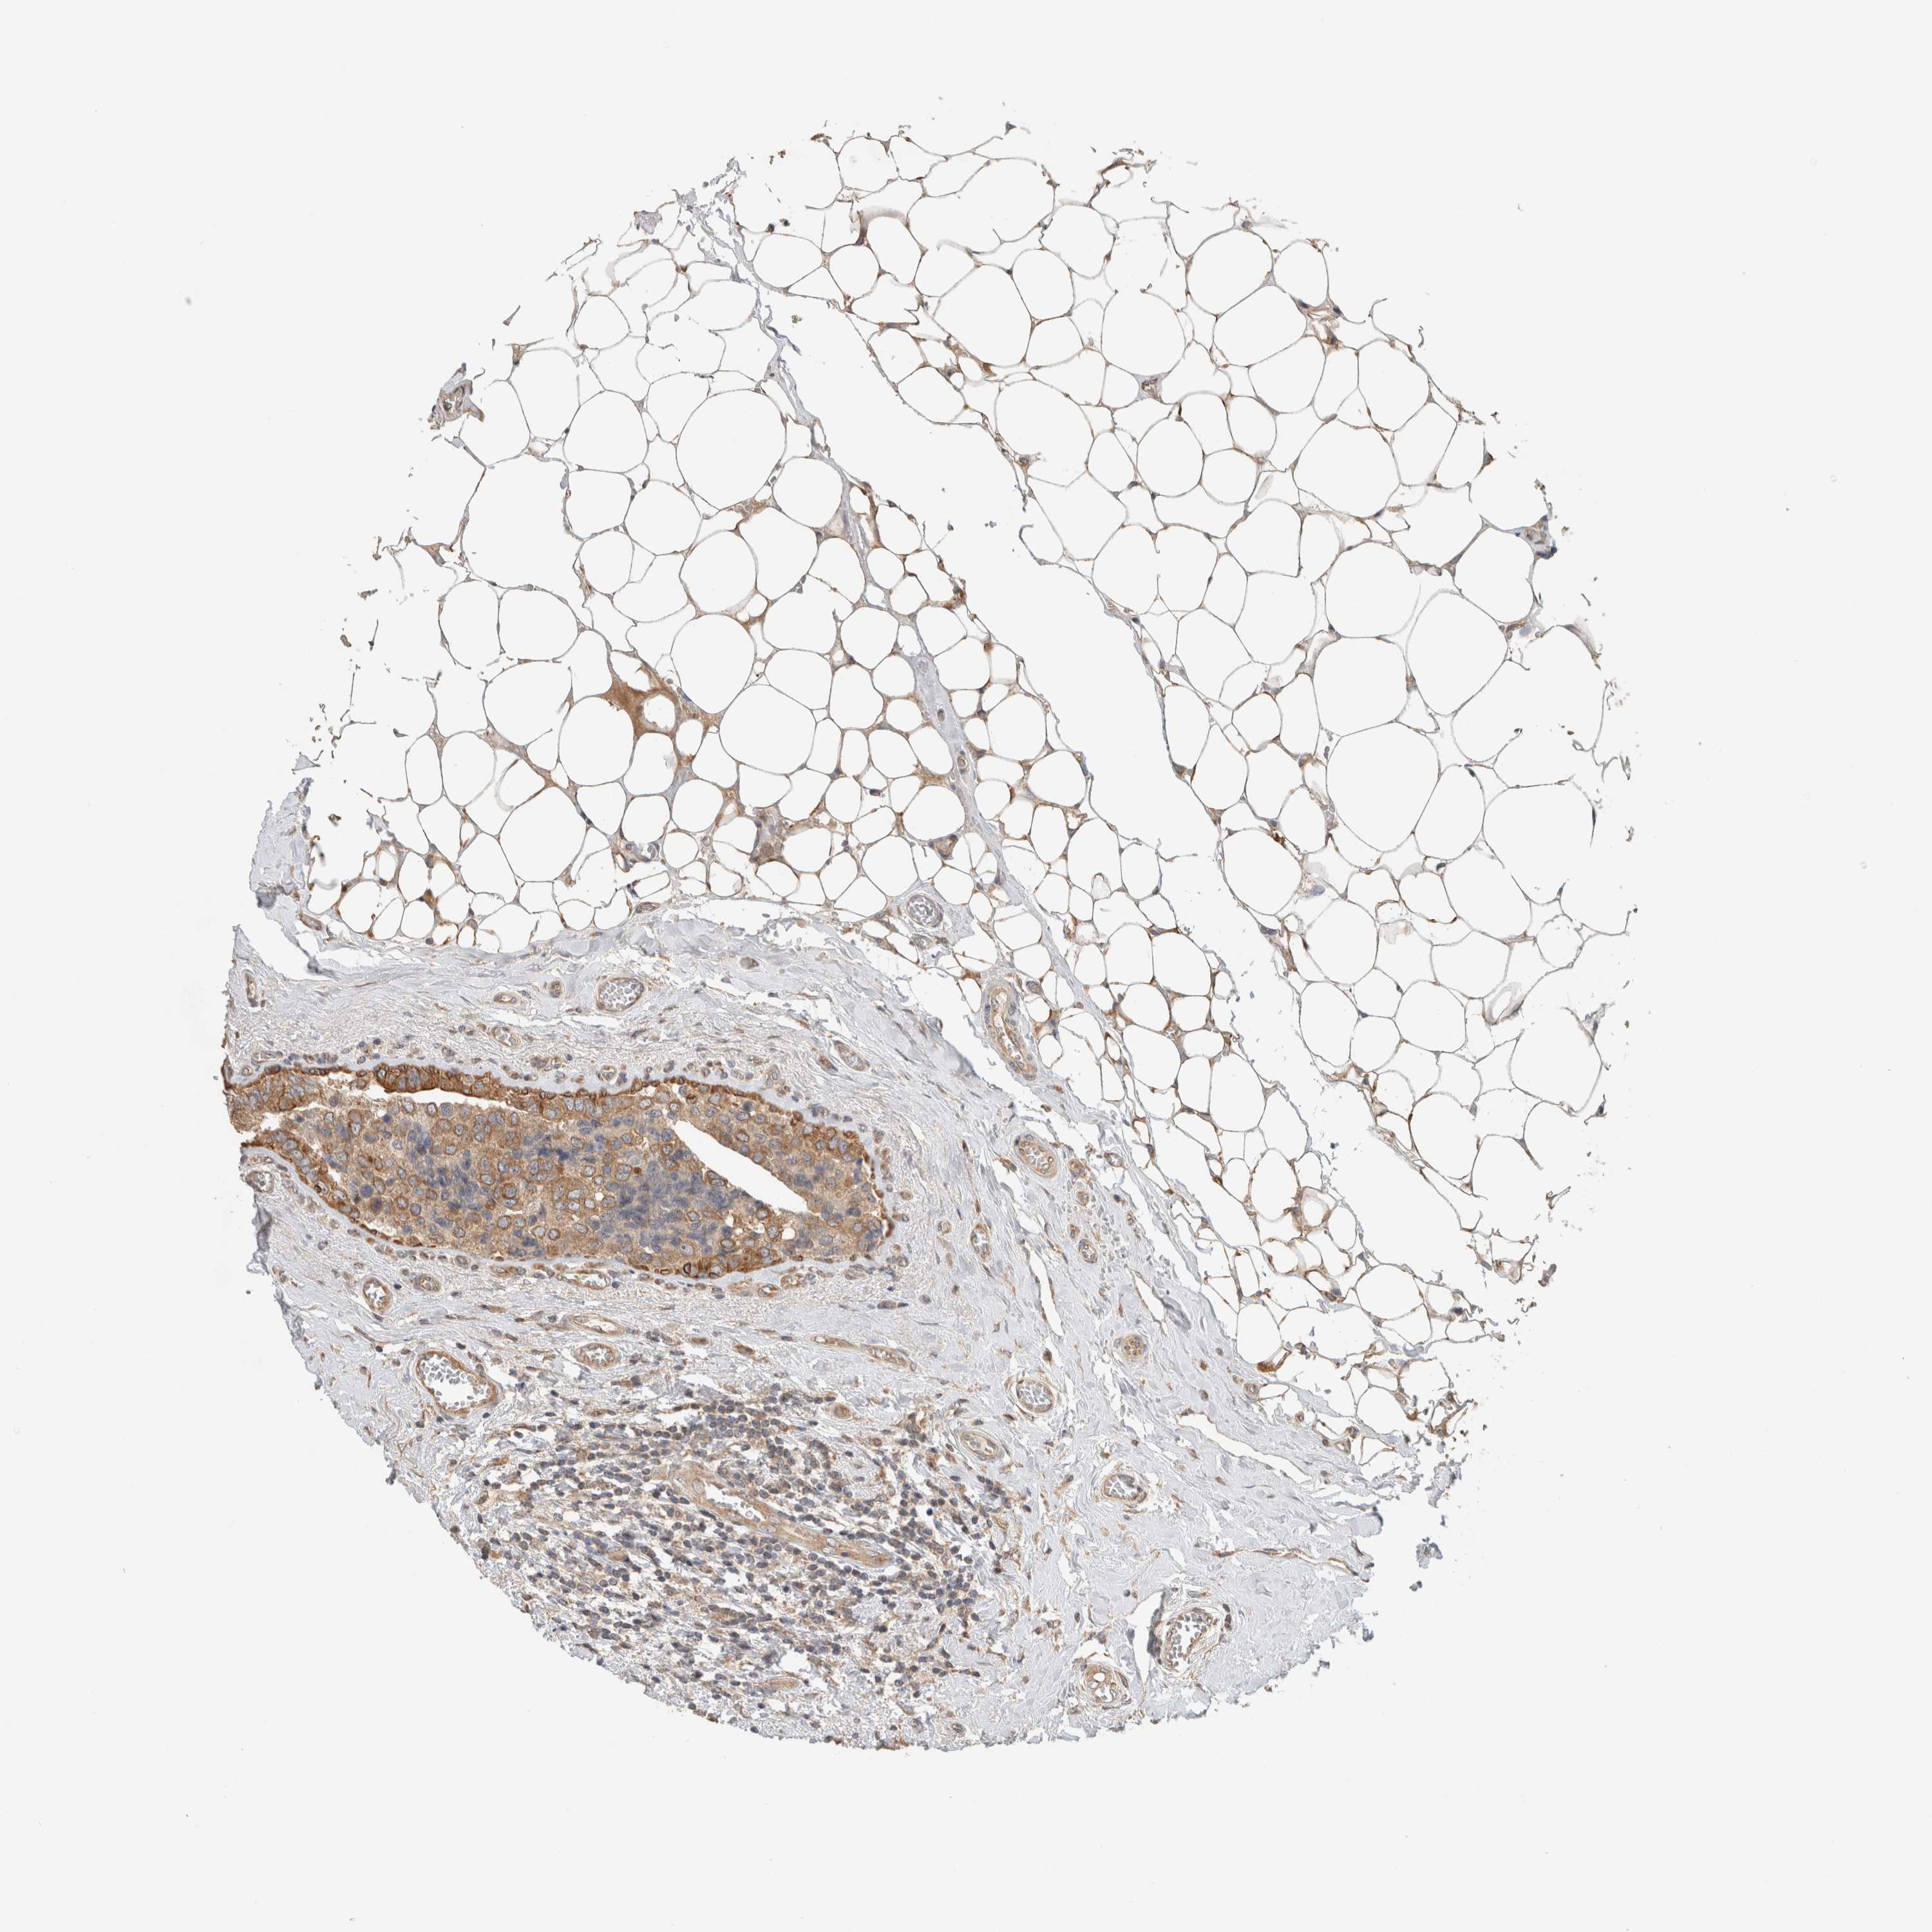

BRCA TCGA BRCA VALIDATION PROTEIN EXPRESSION